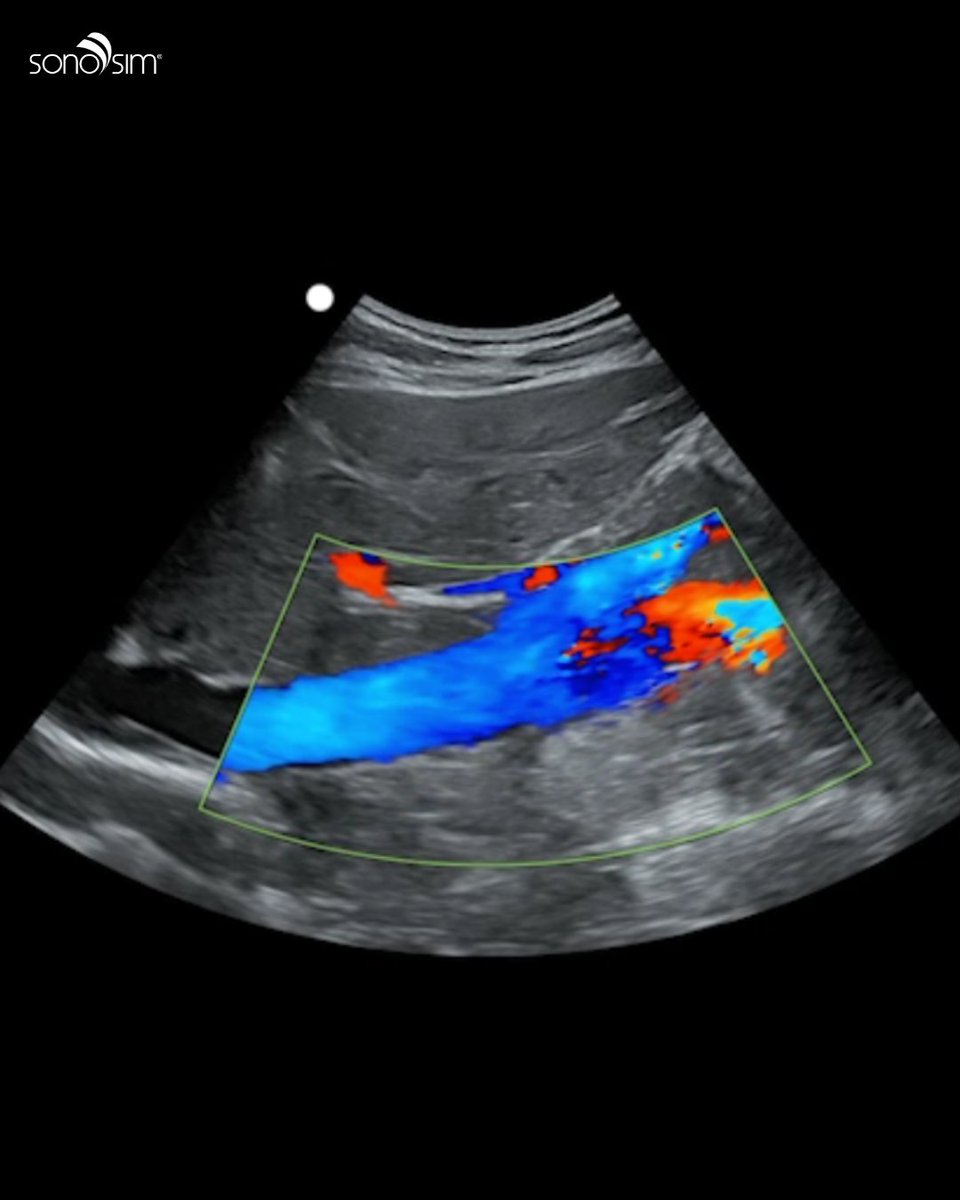

With SonoSim, your next practice session is never limited by a machine, a schedule, or a lab. Just plug in, scan real pathologies, and build skills anywhere your day takes you. ✨